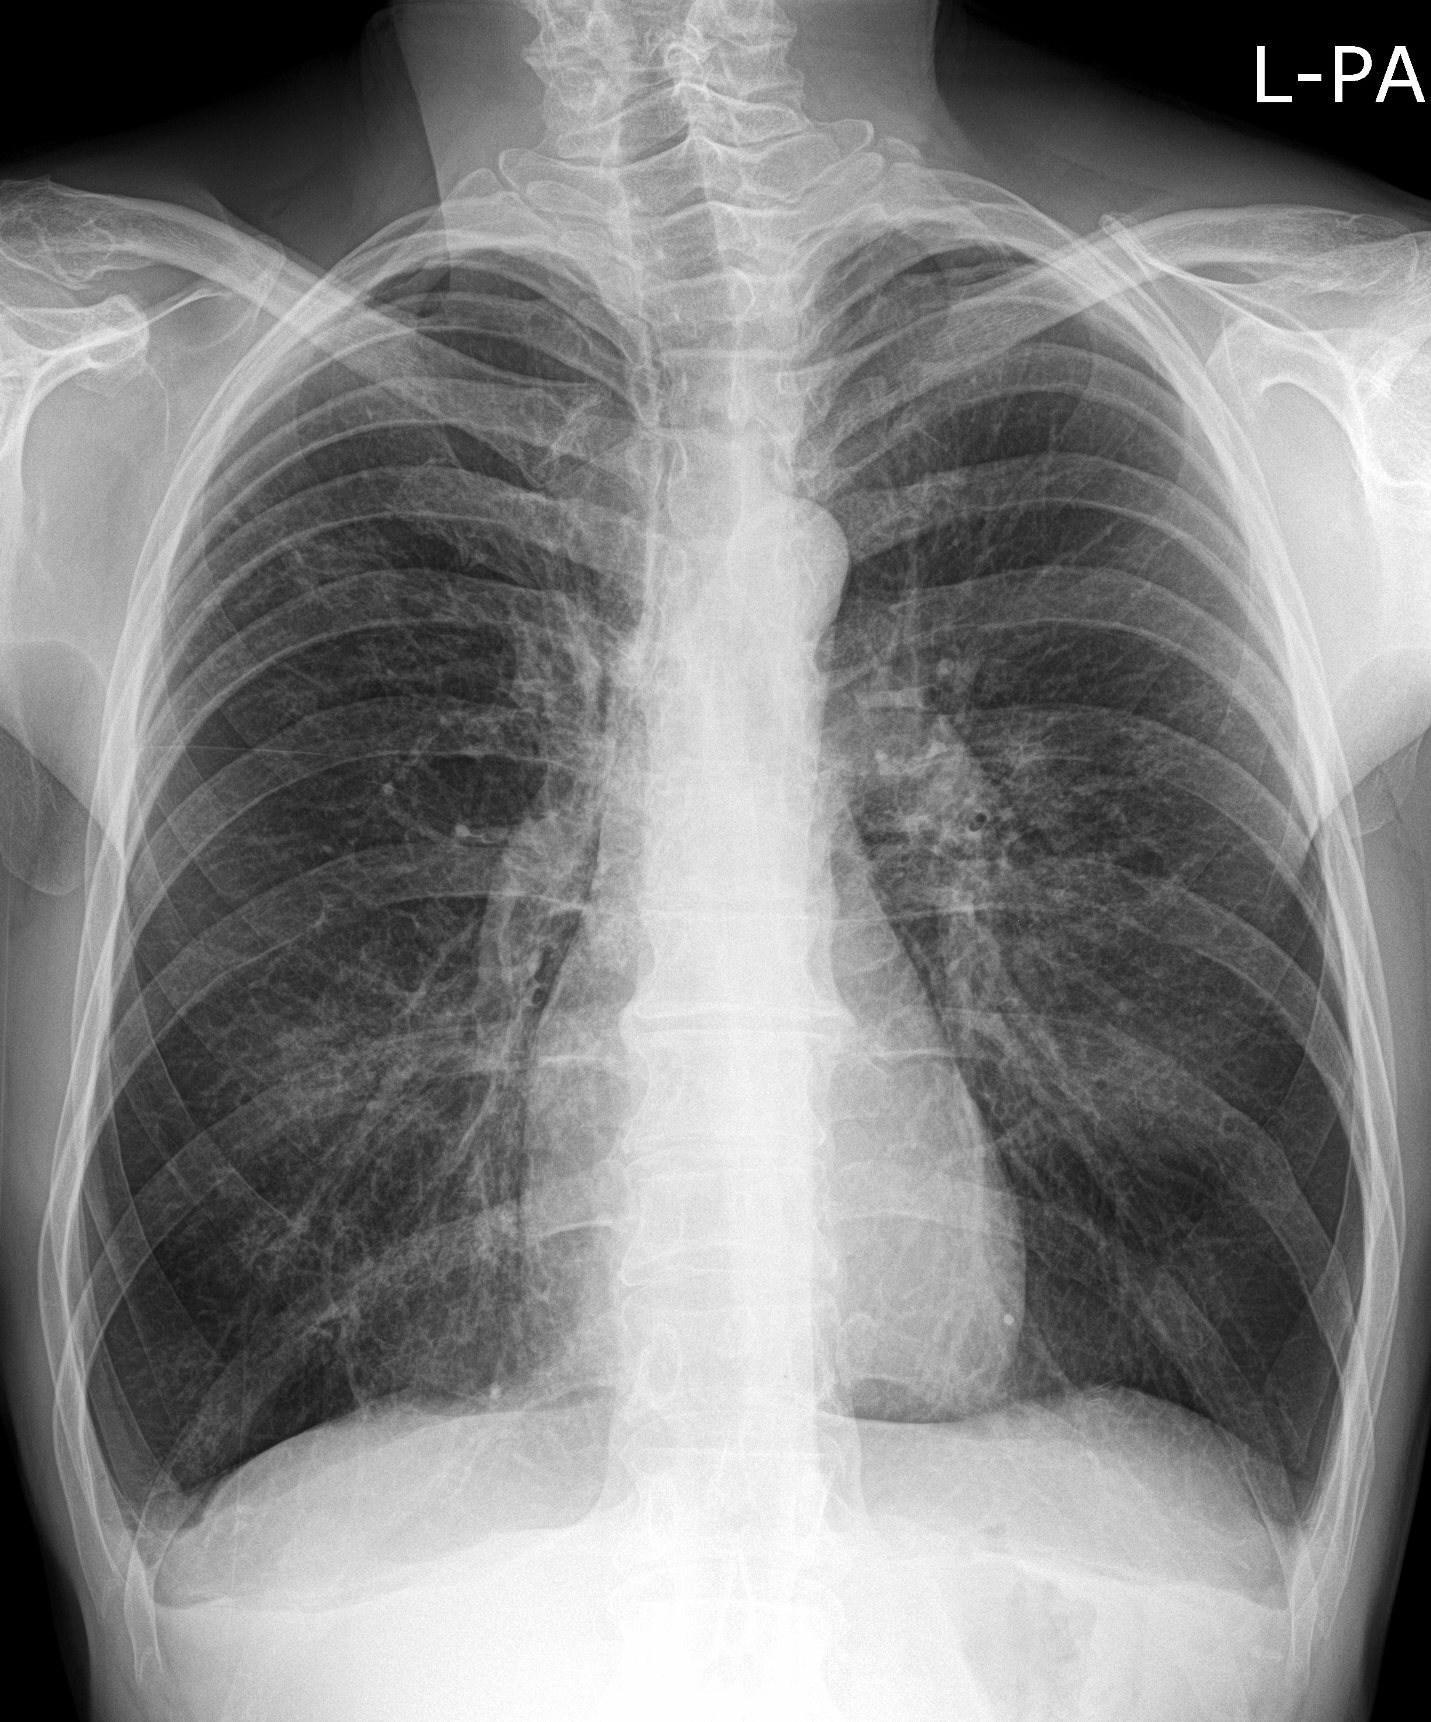

19. Tuberculosis, bidirectional chest radiographs and HRCT. (coronal reconstruction)

75 year old man: hx of hypertension, smoking. Symptoms: dyspnea, productive cough. Moist rales of auscultatory findings above the LLL, tension irritability in the level of lower dorsal spine.

a.) Chest radiograph, bilateral: Mild increased vascular markings. Extensive patchy lobar infiltration in the RUL Previous TB specific lesions in the left apex. The diaphragm contour is blurry on the right side (appr. 4 finger-wide pleural effusion). Cardiomegaly. Medium large dilated sclerotic aorta.

b.) HRCT: Reticular pattern of 10x10x5 cm area in the right apex (1st segment), (septal thickenings), mosaic-like ground glass opacity in the righ apex. Subpleural total atelectasis (mainly 1st segment): irregular mainly nodular soft tissue streak associated with the pleura (max. appr. 1 cm thickness). Some tiny subpleural emphysematous bullae in the right apex.